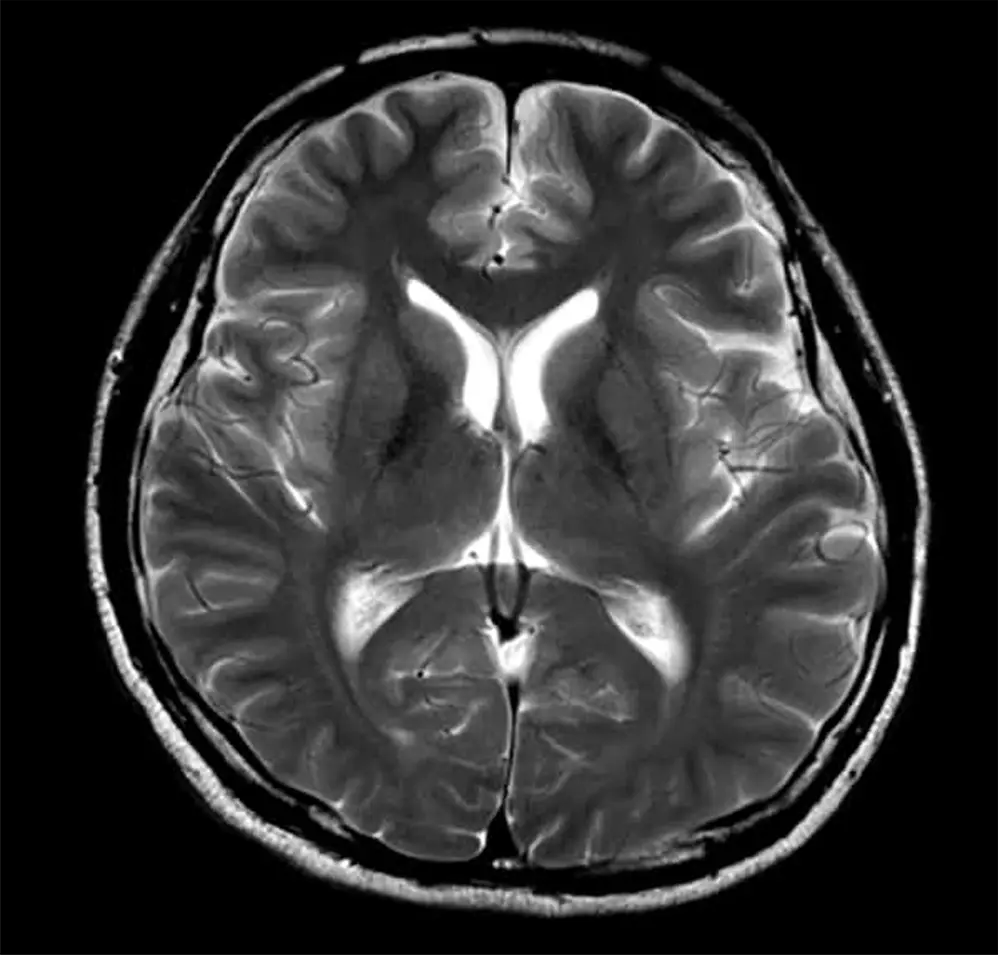

T2強調画像は、水を白く強調するMRIの基本的な撮影方法です。髄液など水成分の多い部位は明るく(白く)映し出されます。

病変部、例えば脳梗塞や脳腫瘍では、組織の障害や浮腫(むくみ)によって水分量が増加するため、その部位が白く描出されます。水や液体成分(髄液、病変部)は白く、脂肪は黒く見えるため、両者を比較することで組織の状態や病変の特徴を総合的に診断できます。解剖学的な構造の評価や病変の検出に広く用いられ、特に脳梗塞では発症時期の推定にも役立ちます。

この2つの脳の画像は同じ50代の人のものです。上の脳画像は、中心にある暗いエリア(脳室という空洞部)が拡大しており、脳の萎縮が進んでいます。脳の萎縮は脳の機能低下や将来の認知症発症のリスク因子と知られています。60歳を過ぎても30代並みの若々しい脳を保っている方の例も多くあり、加齢による萎縮の進み方は人によって大きく異なります。

上の脳画像には白い斑点のようなエリアがあります。

これは白質病変と呼ばれ、脳の血管の健康度の目安になると考えられます。加齢とともに現れる変化ですが、急速な増加は、将来の認知症や脳梗塞のリスク因子と知られています。